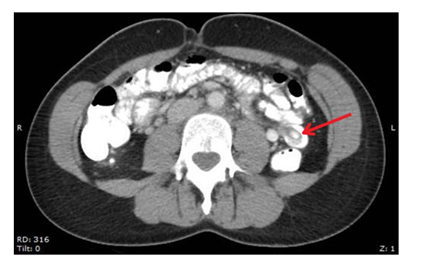

Her physical exam was notable for mild right lower quadrant abdominal tenderness without guarding and periumbilical tenderness without evidence of a palpable mass. Laboratory results were unremarkable with no elevated white blood cell (WBC) count, abnormalities in differentiated complete blood count, or elevated lactate. Her CT abdomen and pelvis with IV and oral contrast revealed an intraluminal oval homogenous mass measuring 1.9x1.1cm in the left hemiabdomen within the mid-jejunum (Figure 1).

Figure 1 Radiographic (CT) image of intussusceptions Radiographic"targetsign".